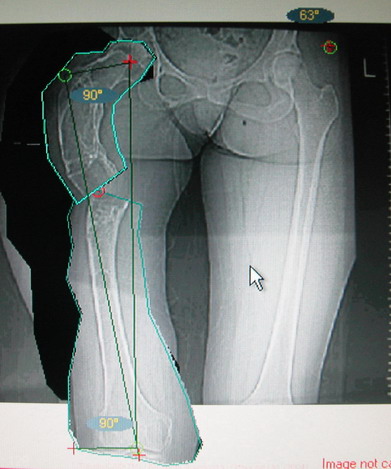

Моё мнение, что двойная остеотомия бедра с аппаратом Илизарова + Гексаподный механизм, или Тэйлора, В данной ситуации является методом выбора. Я очень извеняюсь за качество прилагаемых снимков, в которых я постарался отразить разницу междe одной и двумя остеотомиями бедра.

jo> отразить разницу межде одной и двумя остеотомиями бедра.

Скорее всего, второй уровень может оказаться нелишним лишь при переходе с аппарата на интрамедуллярный стержень. И его не поздно будет пересечь именно в момент введения гвоздя, если будет угроза перфорации стенки канала.

Если сделать фото больного после устранения деформации, вряд ли удастся догадаться, на скольких уровнях она устранялась.

Собственно сустав не беспокоит, объем движений полный. По скиаграммам получается, что достаточно одной остеотомии на вершине деформации, чтобы восстановить длину и вывести коленный сустав в нужное положение.

Т.к. укорочение 7 см, то начинать будем с соеотомии и коррекции аппаратом. Спасибо